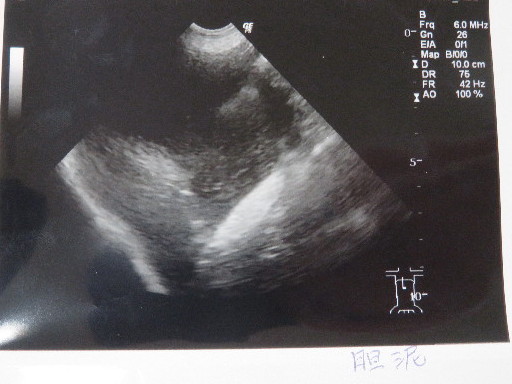

○胆泥はあいかわらずです。

下に濃く溜まっているのと、浮遊しているものと両方。